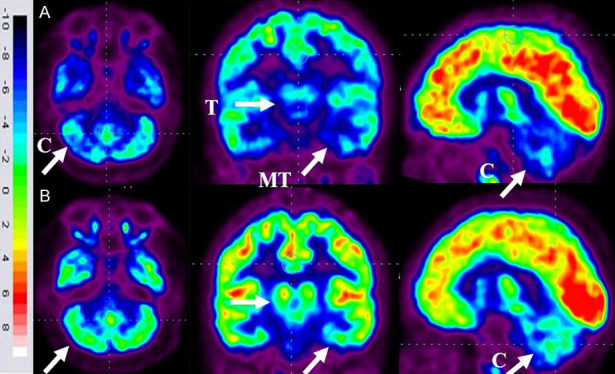

FDG-PET CT掃描腦部對比分析

86名患者的家長同意在干預6個月后重復進行FDG-PET CT掃描以進行比較分析。干預前,這些患者的FDG-PET/CT掃描顯示雙側內側顳葉皮層、丘腦和小腦的代謝活動降低[代謝減退]。此外,它們還表現出尾狀頭、殼核、眶額皮質和前額葉皮質的代謝活動增加(代謝亢進)。

干細胞移植六個月后,所有患者的大腦活動均得到改善。此前,代謝低下區域[內側顳葉皮質、丘腦和小腦]顯示FDG攝取增加,而代謝亢進區域[尾狀頭、殼核、眶額皮質和前額葉皮質]顯示FDG攝取減少(圖6)。在進行T檢驗時,發現干預前后這些區域的平均SUV出現了統計學上的顯著變化[P<0.05]。

圖6:ASD患者在細胞治療前和細胞治療后6個月進行的FDG-PET/CT大腦掃描的代表性圖像。

A.頂行:標有箭頭的藍色區域表明代謝低下。B. 下排:用箭頭標記的綠色區域表明細胞移植后新陳代謝得到改善。